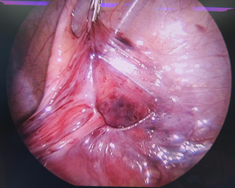

治療には、体にかかる負担をより小さく、手術創もより小さくするような「低侵襲治療」を実践するため、腹腔鏡手術を積極的に行っており、日々新しい知見を取り入れ、常に最善の治療を目指し、「患者様に信頼される小児外科チーム」になるように努力しております。

抗生剤の点滴のみによる治療もありますが、最終的に手術が必要になることが多いです。当科では、お腹に小さい孔を数カ所あける腹腔鏡手術を積極的に行っており、症例をみて臍の創のみで手術を行う単孔式腹腔鏡手術も行っています。